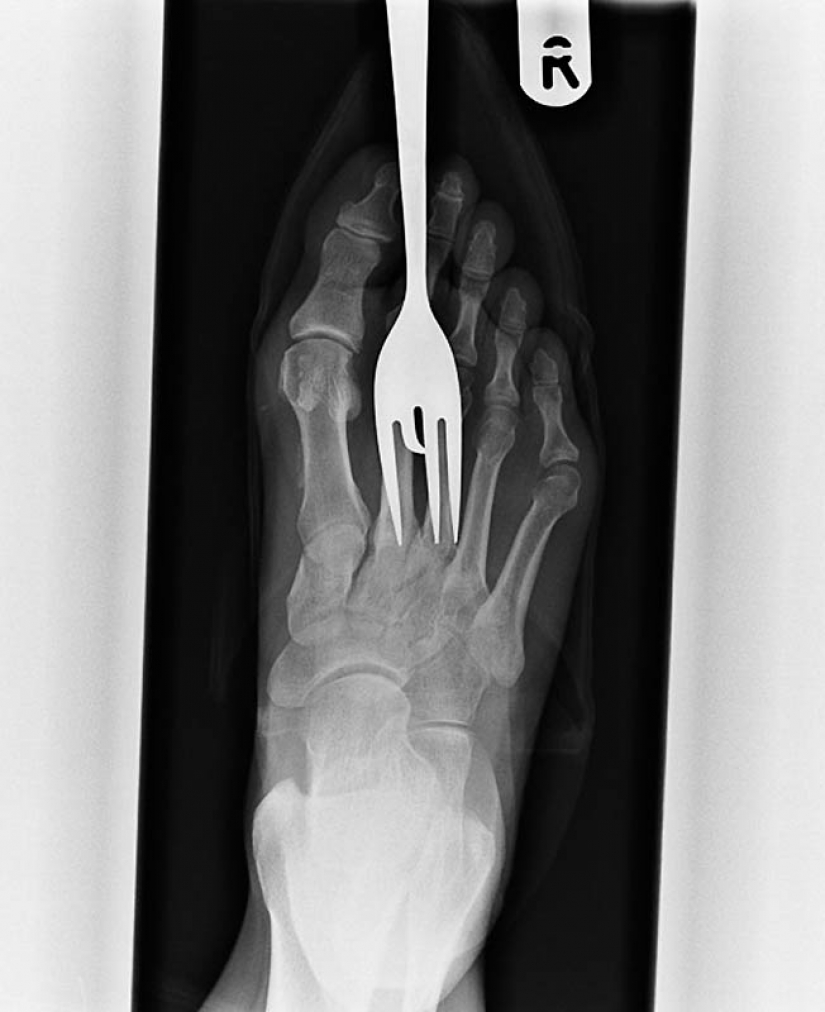

7. X-ray of a patient who stepped on a fork.

10. Another patient stepped on a fork.